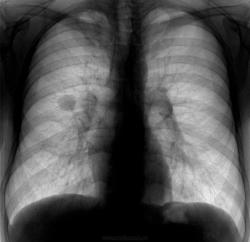

Бомжеватого вида молодой человек, вспомнив о двух детках, решил устроиться на работу, требует положительной флгр. Жалоб не предъявляет, архива нет. Предыдущая Ro-гр.ОГК - 2 года назад в наркодиспансере, где выходил из запоя. По его словам - было все ОК. Что-то есть справа в S1. А что это за гомогенноинтенсивночеткий кругляшок, да еще (если пофантазировать) с дренажным сосудиком? Какая-то киста, или что-то посерьезней. Если допустить, что на верхушке фиброзноочаговые изм., а второе - киста - можно и отпустить с богом. Все равно (по его словам) денег на КТ ОГК, консультации (особенно в онко) нет. Пожалеть деток?

Не внушает мне эта тень «фейсно», как отражение периферического рака, никакого доверия и симпатии.